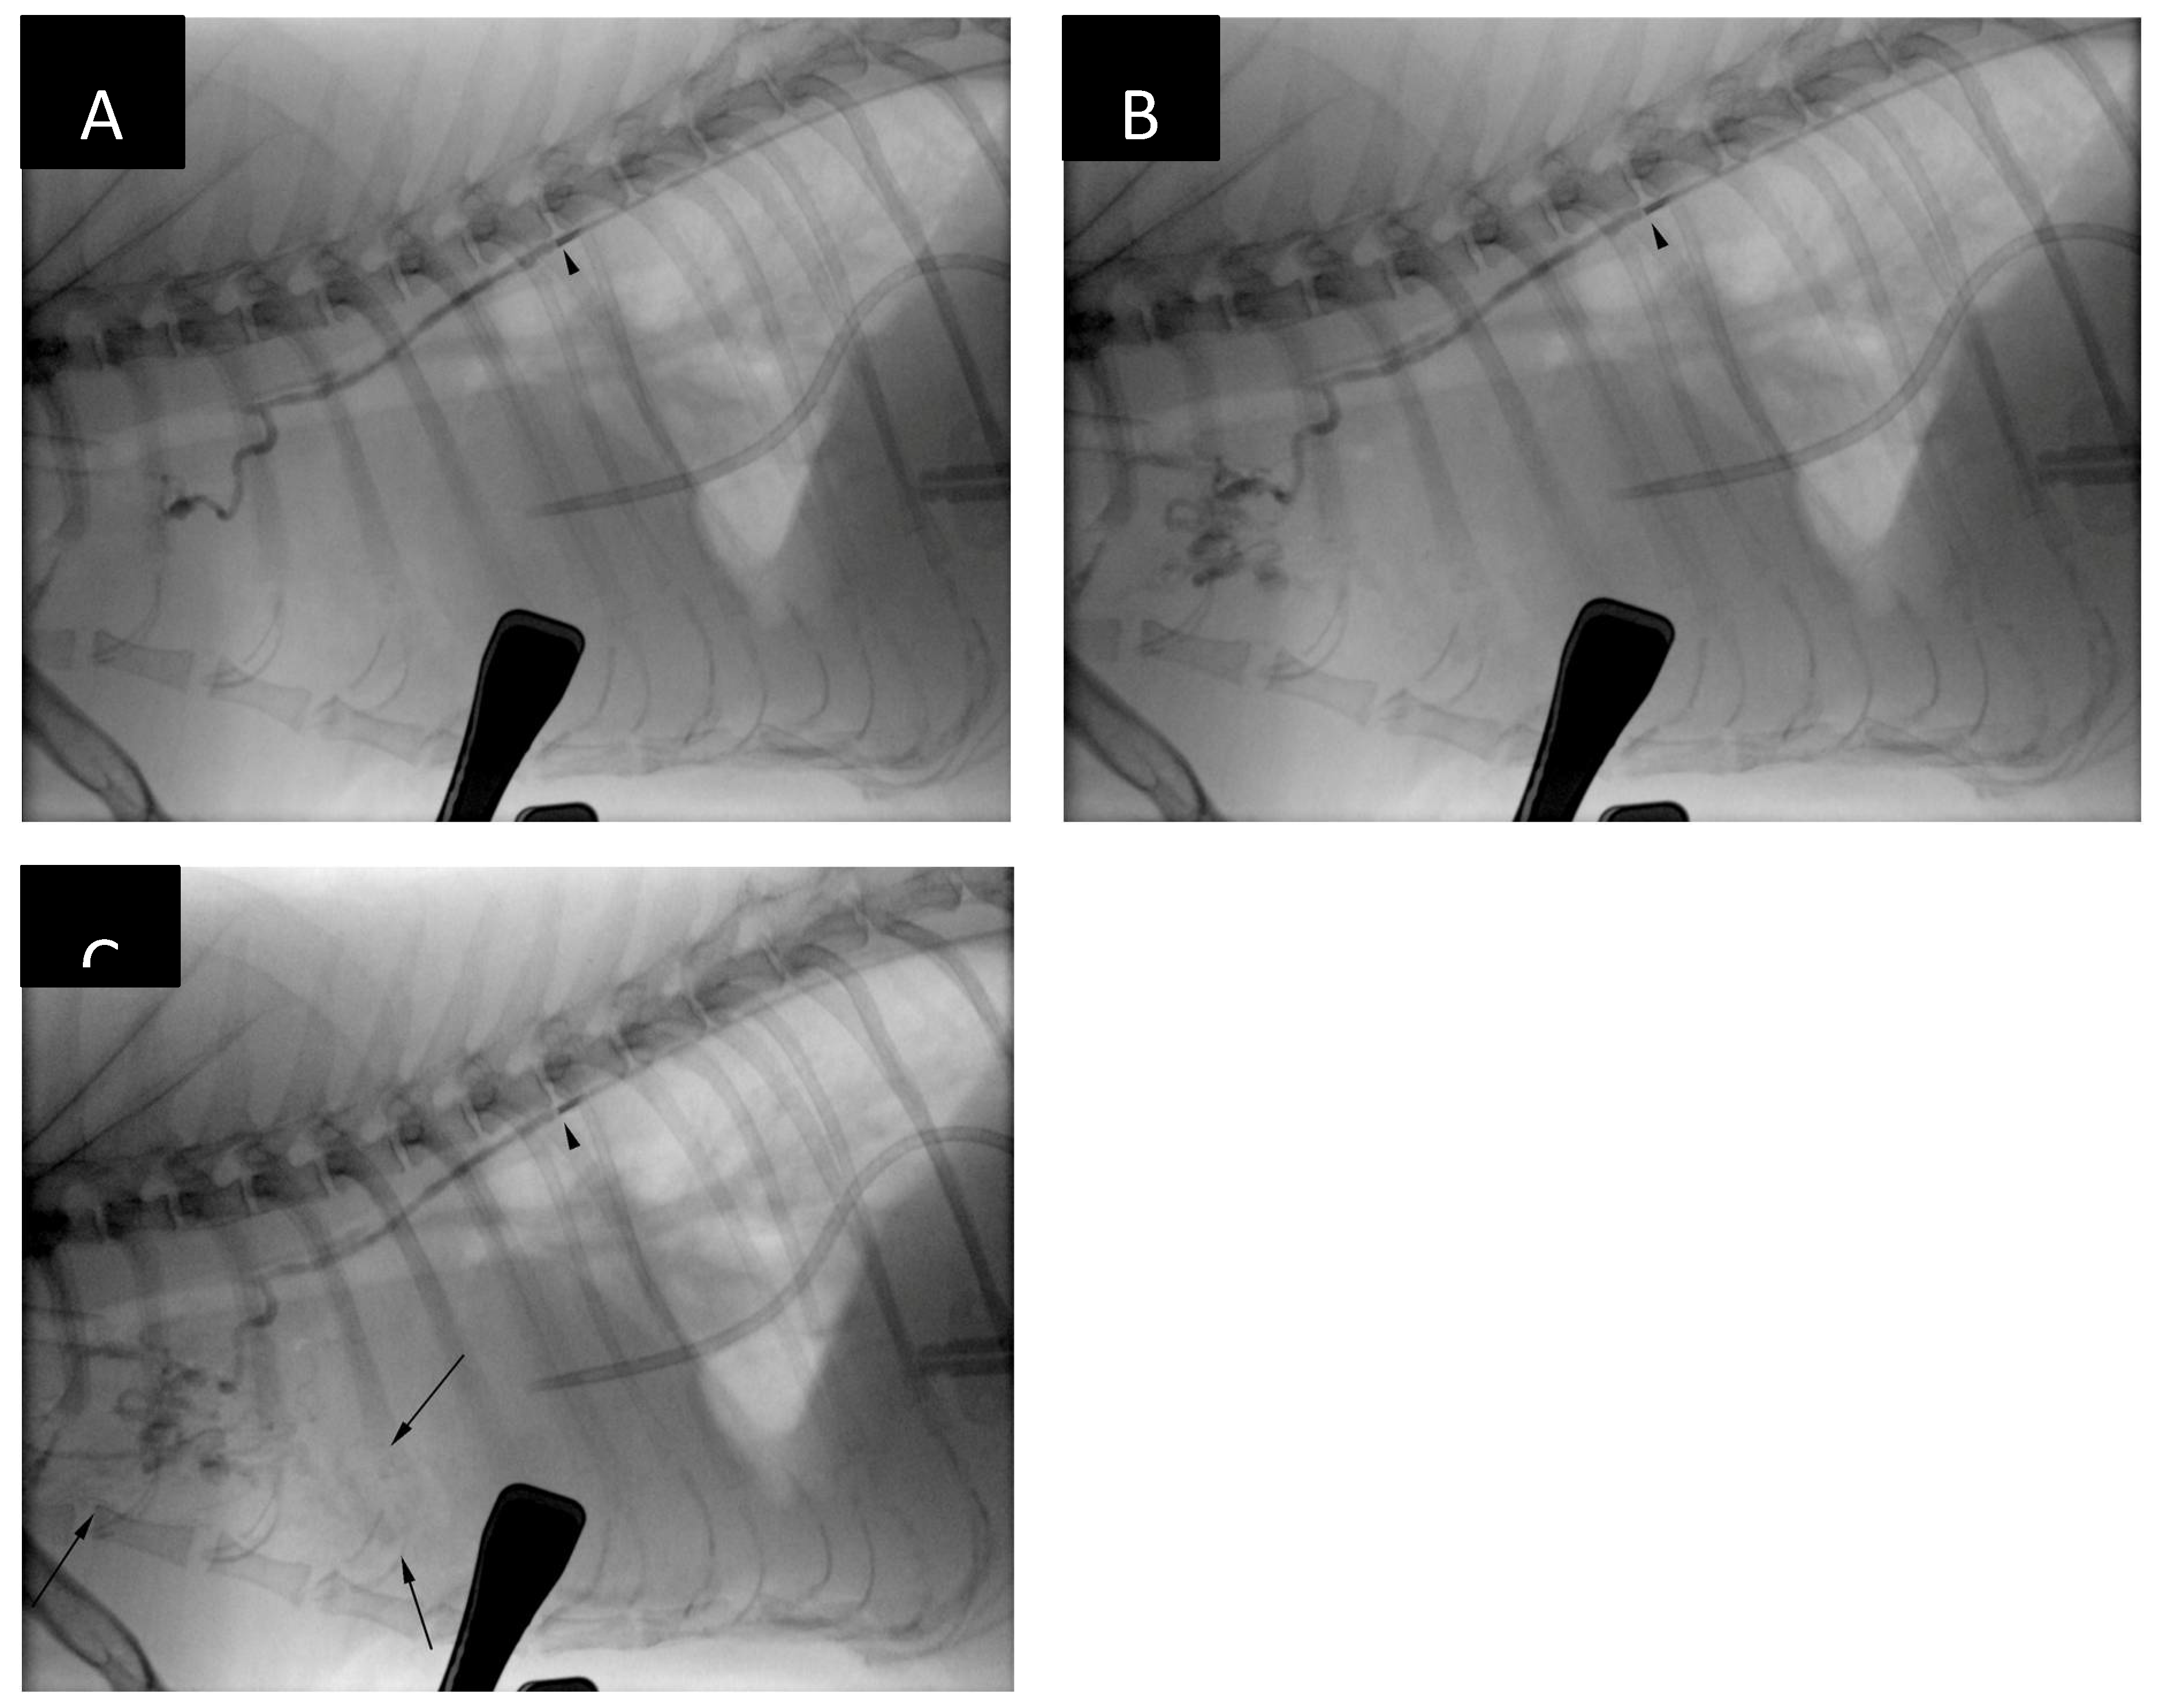

During a follow-up consultation on day 8 post-TDE an increase in respiratory rate (40/min) with abdominal ’push’ were noted. Abdominal cavity appeared distended. Thoracic x-rays (Figure 10) revealed mild to moderate pleural effusion and distension of the caudal vena cava. There was no evidence of presence of embolic material within the pulmonary circulation. However, there was mild amount of radiopaque material visible cranial to the cardiac silhouette on the lateral view which was presumed to represent either non-target mediastinal embolization or accumulation of the ethiodized oil within of the mediastinal lymph node(s). Presence of the ‘embolus’ in the periaortic and cranial mediastinal lymph nodes was noted in all dogs on 12 weeks follow-up CTLA in Carvajal’s et al. study [16].

Figure 10. Thoracic radiographs in left lateral (A) and dorsal (B) recumbency 8 days post-TDE. Two parallel thoracic duct branches cranial to the coil pack can be appreciated (white arrows). Additional serpentine-like thoracic duct branch at the level of the T13-L1 intervertebral disc space (black arrows) can also be seen. This branch was not visualized during the embolization procedure. There is accumulation of radiopaque material cranial to the cardiac silhouette (panel A, black circle). There is no evidence of glue:ethiodized oil embolization into the pulmonary vasculature. The most cranial portion of the glue embolus appears less radiopaque than immediately after the embolization procedure. Similar findings have been described by Pardo et. al (3).